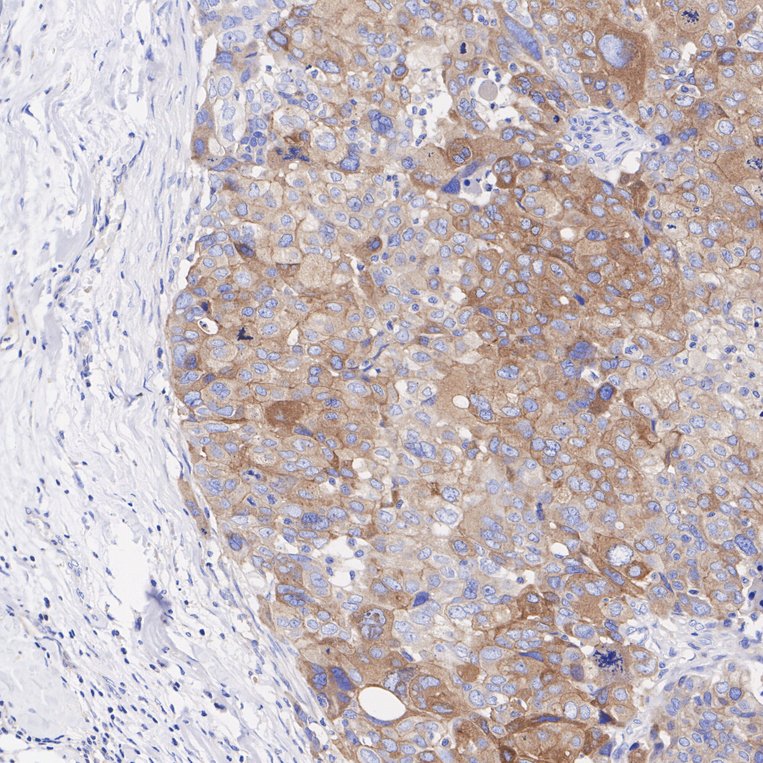

Immunohistochemical analysis of paraffin-embedded human ovary carcinoma tissue with Rabbit anti-Met (C-Met) antibody (ET1606-45) at 1/1,000 dilution.

The section was pre-treated using heat mediated antigen retrieval with Tris-EDTA buffer (pH 9.0) for 20 minutes. The tissues were blocked in 1% BSA for 20 minutes at room temperature, washed with ddH2O and PBS, and then probed with the primary antibody (ET1606-45) at 1/1,000 dilution for 1 hour at room temperature. The detection was performed using an HRP conjugated compact polymer system. DAB was used as the chromogen. Tissues were counterstained with hematoxylin and mounted with DPX.